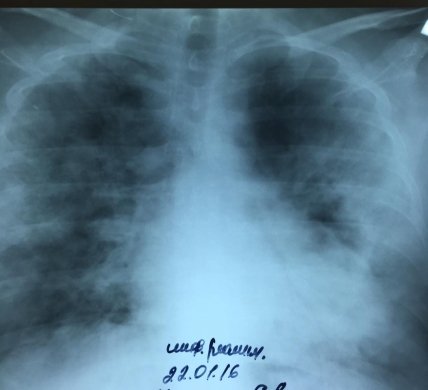

Вот очередной снимок пациента 34 лет, поступившего вчера в 5 утра на 6-ой (!) день болезни с сатурацией (насыщение артериальной крови кислородом) до 40% (кто не знает, в норме до 100%). К сожалению, сегодня его уже нет.